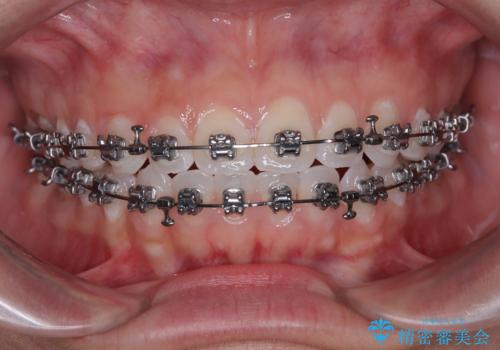

- メタルブラケット

- 上下前歯のデコボコを気にして来院された患者様です。

ワイヤー矯正でもマウスピース矯正でも可能でしたが、短期間で、自身の手を煩わせることなく治療を行いたいとのことで、ワイヤー装置にて矯正治療を行うこととしました。

僅か半年強、あっという間に治療を終えることができました。